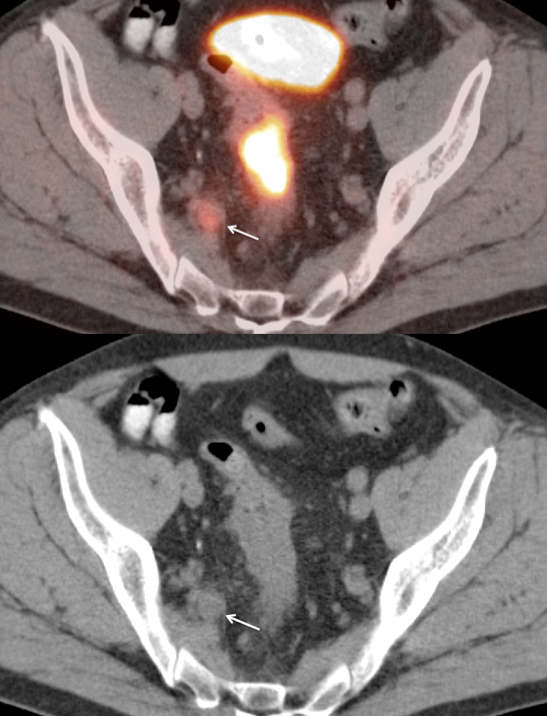

Presentation of Primary Cancer

• Focal bowel uptake, usually with associated bowel wall thickening.

• Normal physiologic bowel uptake (discussed here) can be very focal and isolated to only one part of the colon, most commonly the cecum and rectum. Always look for associated bowel wall thickening on the CT images.

• Beware the small rectal cancer!  As the ano-rectal region frequently demonstrates intense physiologic uptake, it is very easy to overlook a rectal malignancy, especially if it is an incidental finding.  To avoid this error, always evaluate the rectum carefully on the sagittal whole body images.  It is shocking to see how readily apparent a rectal cancer can be on these images, yet so easily overlooked in the axial plane.